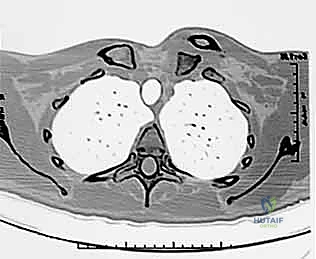

- التصوير المقطعي المحوسب (CT Scan) - المعيار الذهبي: يؤكد الدكتور هطيف أن الأشعة المقطعية، خاصة مع إعادة البناء ثلاثي الأبعاد (3D Reconstruction)، هي الإجراء الحاسم. فهي تحدد بدقة متناهية اتجاه الخلع، وجود كسور مصاحبة، ومدى قرب الترقوة من الهياكل الحيوية.